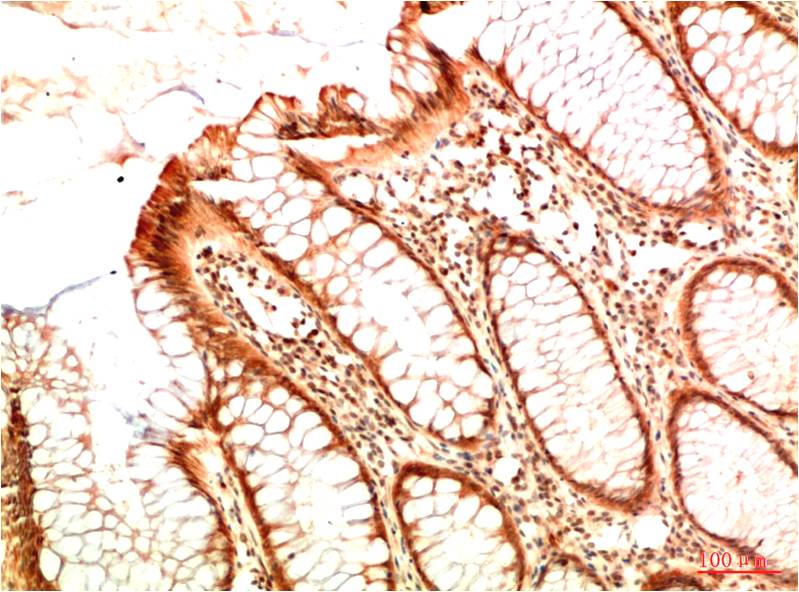

Acetyl P53(K382) Mouse Monoclonal Antibody(5H10)

Applications :IHC

| Recommended dilutions: | IHC: 1:100-200 |

| Specificity: | The Acetyl P53(K382) Mouse Monoclonal Antibody can detects endogenous Acetyl P53(K382) proteins. |